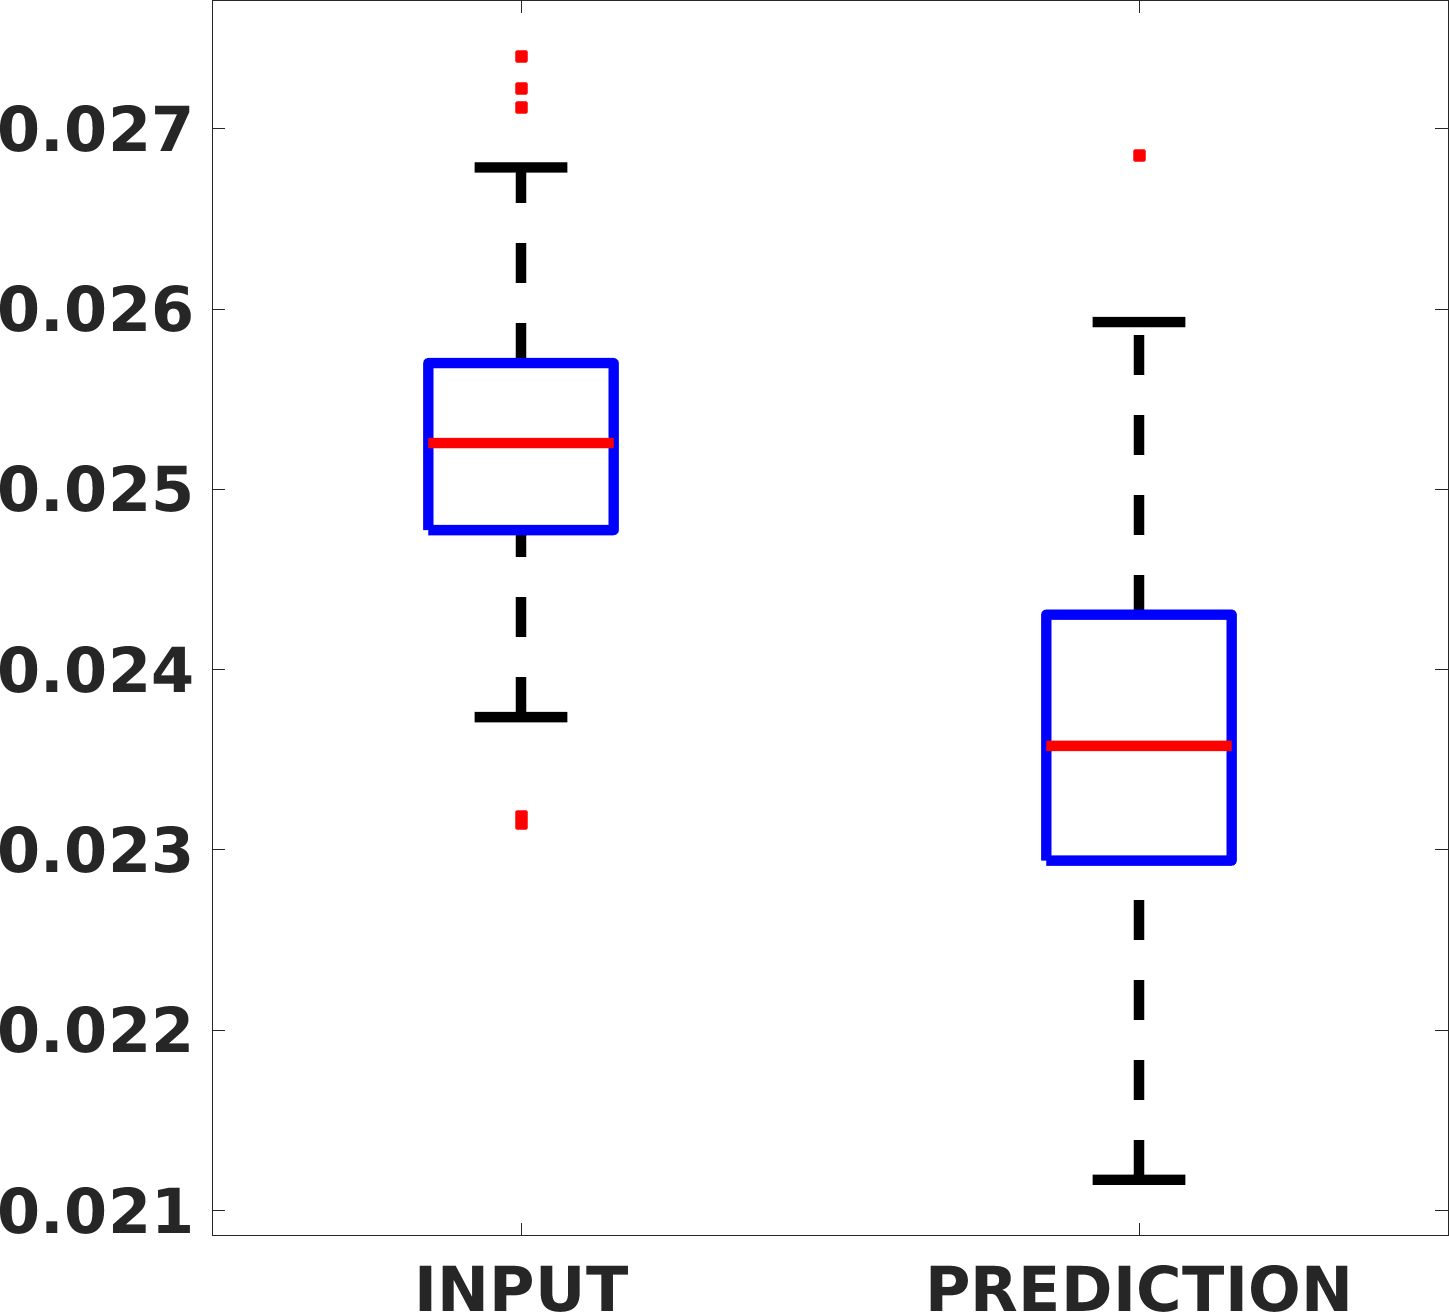

Fig. 8 shows the box plot of the SSIM (a-b-c, left) and MAE (a-b-c, right) quantitative metrics, as performed for PSNR metric. Also, these metrics show that our method improves the results of Cubic convolution both in terms of average value and variability. For example, the SSIM median value improves of on obstetric 4X images and the MAE median value improves of on cardiac 2X images.

Fig. 17 (left) shows the box plot of the quantitative metrics, comparing the target images with the prediction and the Cubic convolution, respectively. The PSNR metric is computed on a data set of 200 images, belonging to the same district, and with the same up-sampling factor. Analysing the obstetric anatomical district and concerning the corresponding raw images (Fig. 7 (a, left)), the denoising allows the network to significantly improve the results of the up-sampling and the prediction. In particular, comparing the target images with the predicted images, the median PSNR value of obstetric 2X denoised images is 51.8, compared to the median PSNR value of obstetric 2X raw images which is 36.9.

Fig. 17 (right) shows the histogram of the absolute value of the error with respect to the target, of the prediction and Cubic convolution respectively. This result shows that our framework increase of and (2X and 4X, respectively) the number of pixels where the prediction error is lower than 5, which is very similar to the target when visually analysing the images, and improved with respect to the learning framework applied to raw images. According to Fig. 18, our method improves the accuracy of Cubic convolution. For example, the SSIM increases of on cardiac 2X and the MAE increases of on abdominal 4X.